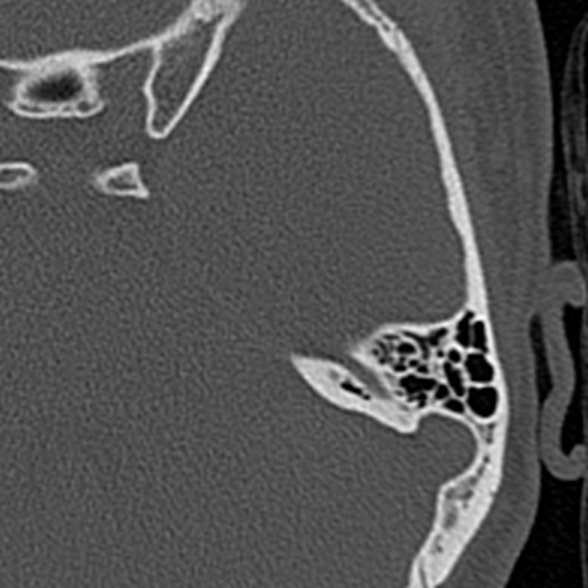

CT Temporal Bone Axial